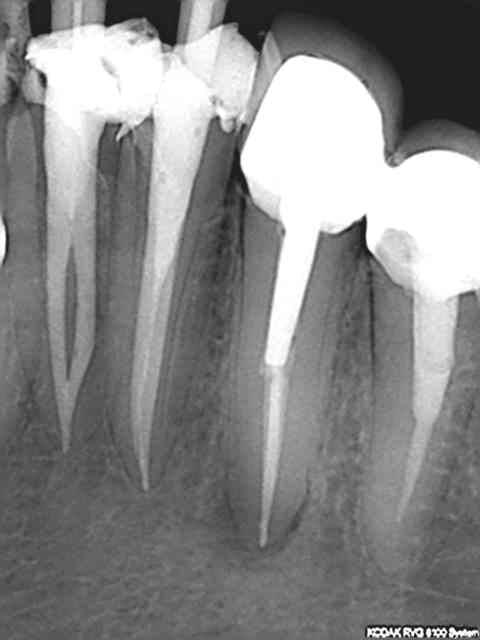

Sauf que si le mec développe une grosse pêche et dit que ce n'est pas par hygiène négligente mais parce que tu as bossé comme un sagouin, et qu'il porte plainte pour ça, on va te reprocher de pas avoir suivit les recommandations de bonne pratique (pas de clamp sur la radio, obturation à chier, etc), et ce sera à ta responsabilité pour faute et ta RCP de casquer (donc à toi indirectement, via augmentation des primes). Perte de chance, tout ça.

On fait tous avec, mais c'est une dévalorisation de nos compétences. On pourrait faire tellement mieux. Et on se retrouve à faire de l'endo rapido+IC+CCM sur grosse carie parce que c'est remboursé. Ca marche aussi, remarque. C'est juste dépassé et délabrant. Et retour au sujet initial.... qui tourne un peu en rond ;)